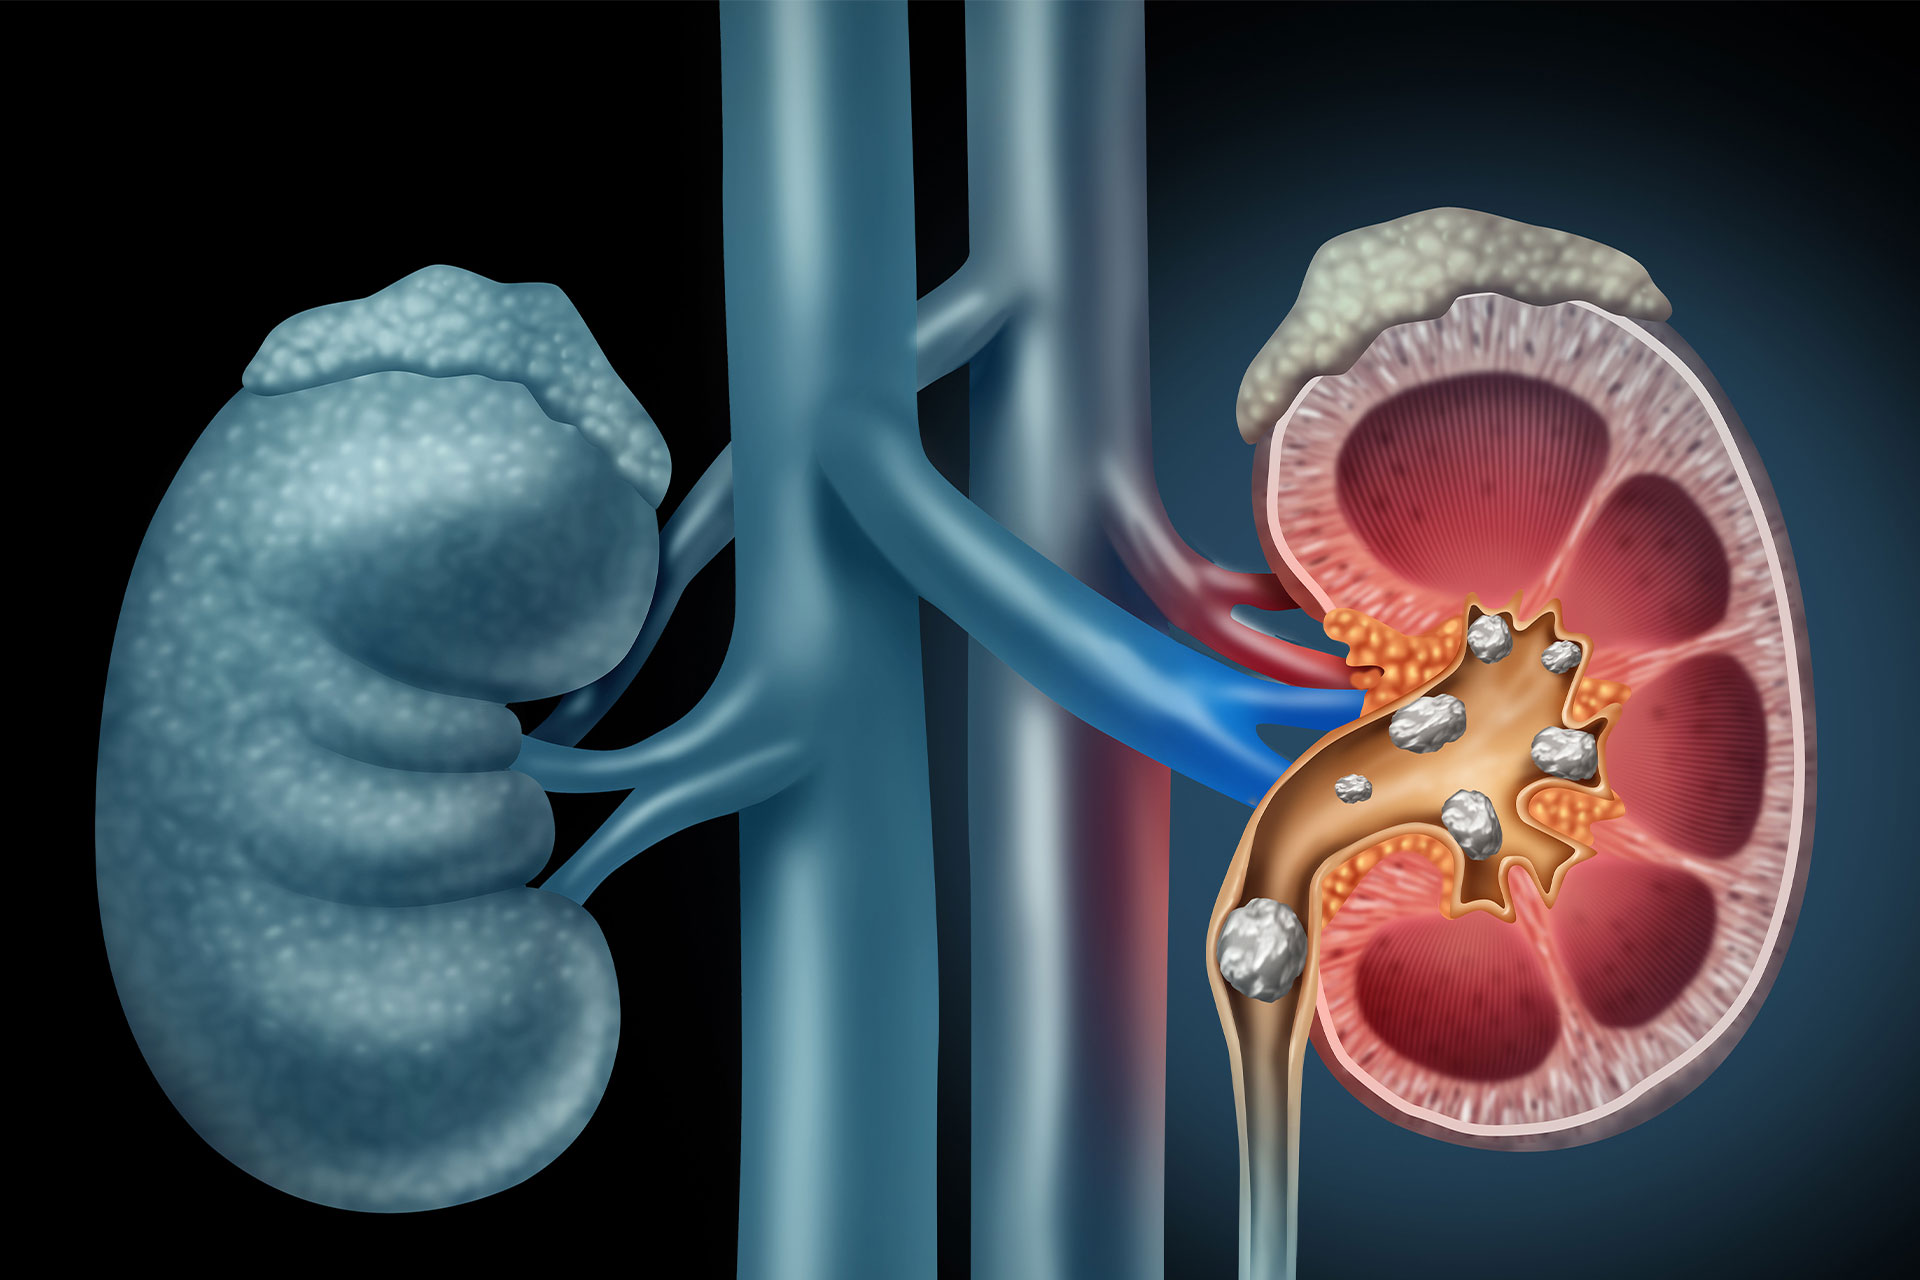

Dr. Lokendra Kumar General and Laparoscopic Surgeon with special interest in Cancer surgery, Gastro ( G.I) surgery and Minimal invasive surgery, More than 14 years of experience in the field expertise in Laparoscopic appendix surgery, Laparoscopic gall bladder surgery, Laparoscopic hernia surgery, Laparoscopic Gastro Surgery, Laparoscopic abdominal surgery, colorectal surgery, thyroid Surgery, varicose veins Surgery, Stone surgery, piles surgery, fistula and fissure Surgery.